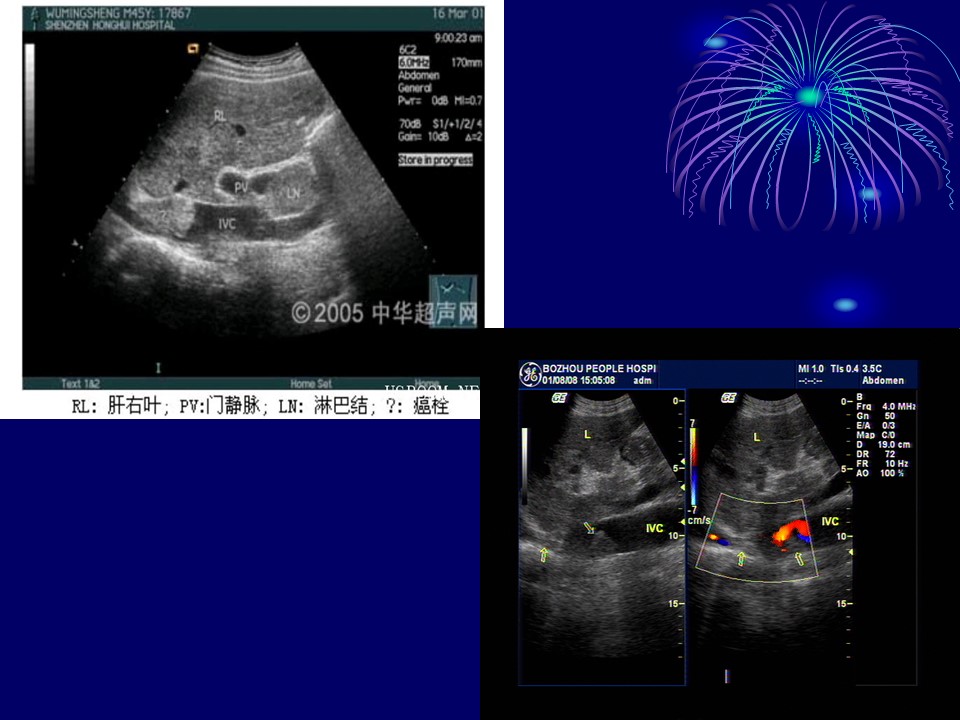

“布加综合征BCS超声诊断PPT” 的相关文章